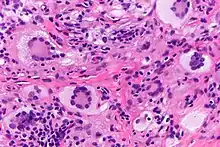

Touton giant cells in a juvenile xanthogranuloma. H&E stain.

Touton giant cells, being multinucleated giant cells, can be distinguished by the presence of several nuclei in a distinct pattern. They contain a ring of nuclei surrounding a central homogeneous cytoplasm, while foamy cytoplasm surrounds the nuclei.[4][5] The cytoplasm surrounded by the nuclei has been described as both amphophilic and eosinophilic, while the cytoplasm near the periphery of the cell is pale and foamy in appearance.[6]